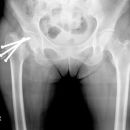

pertrochantäre Femurfraktur